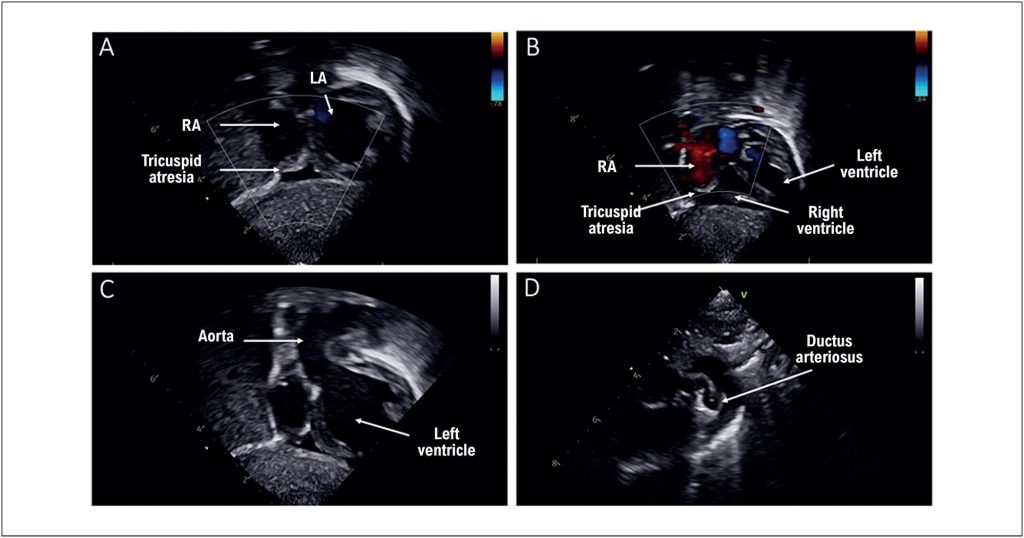

Tricuspid atresia with pulmonary atresia is a rare congenital heart defect, representing about 1% to 3% of all congenital heart diseases. Tricuspid atresia is subdivided into type I (normal position of the great arteries) and type II (transposition of the great arteries), with type 1A characterized by the presence of associated pulmonary atresia or stenosis. Pulmonary blood flow in these patients is dependent on the patency of the ductus arteriosus, making its maintenance essential in the neonatal period.

The treatment of tricuspid atresia follows a staged surgical approach, aiming for a Fontan circulation as the final goal. In the neonatal period, the focus is to ensure adequate pulmonary blood flow through hemodynamic or surgical interventions, including systemic-pulmonary shunts or ductal interventions.